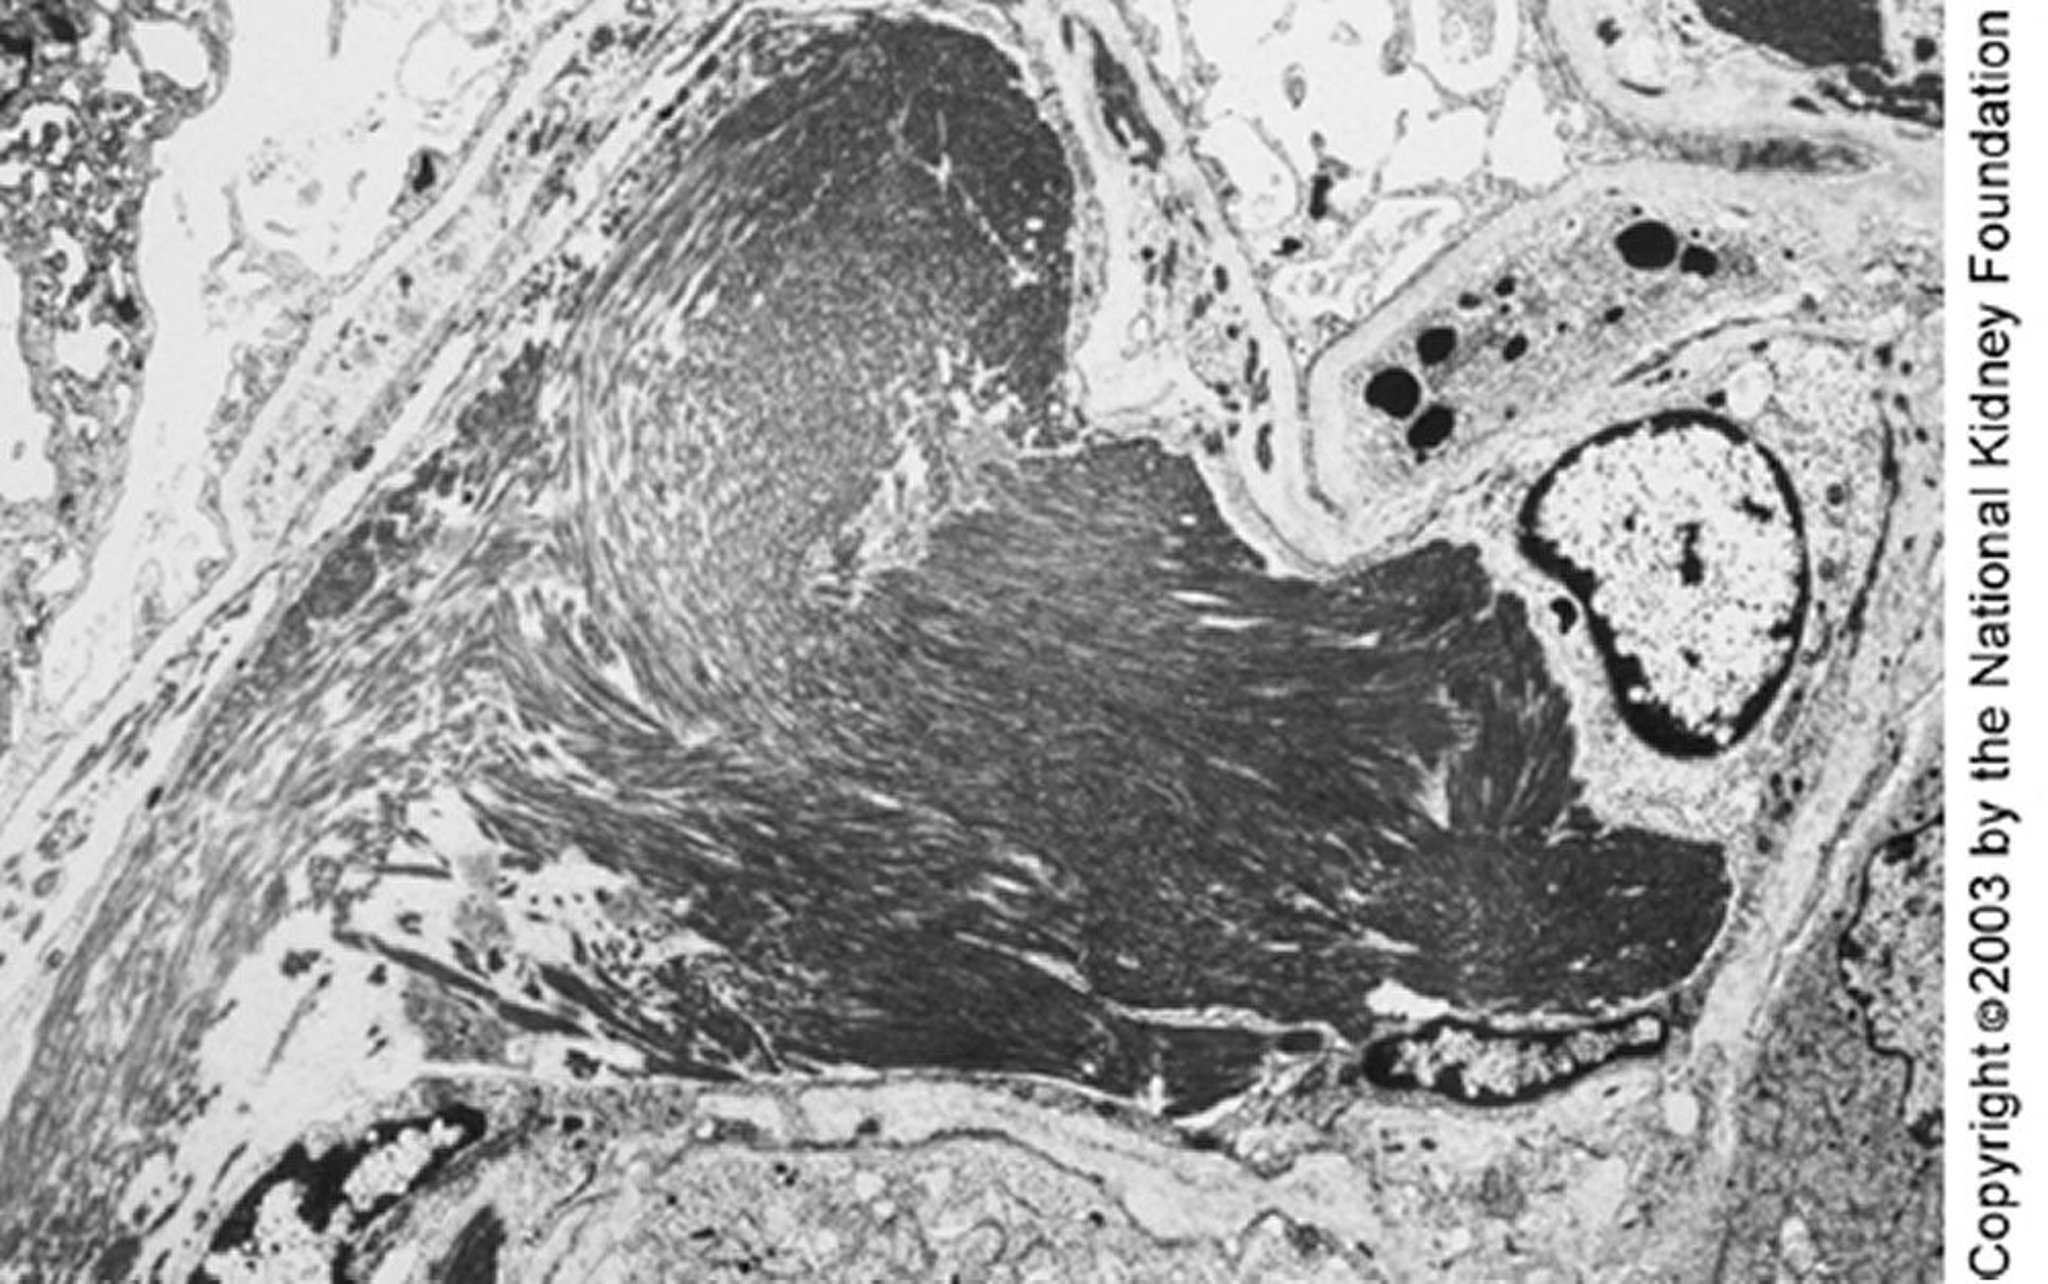

Grandi microtubuli (circa 50 nm di diametro) organizzati in matrici parallele possono essere visti alla microscopia elettronica a trasmissione. I depositi paralleli e la struttura microtubulare possono permettere di distinguere la glomerulopatia immunotattoide da quella fibrillare (×4000).

Imagine fornita da Agnes Fogo, MD, and the American Journal of Kidney Diseases' Atlas of Renal Pathology (vedi www.ajkd.org).

Alcuni esperti distinguono la glomerulopatia immunotattoide da quella fibrillare in base alla presenza di strutture microtubulari (al contrario delle più piccole microfibrillari) nei depositi; altri le distinguono per la presenza di una malattia sistemica correlata. Per esempio, una malattia linfoproliferativa, gammopatia monoclonale, crioglobulinemia, o lupus eritematoso sistemico possono suggerire una glomerulopatia immunotattoide.